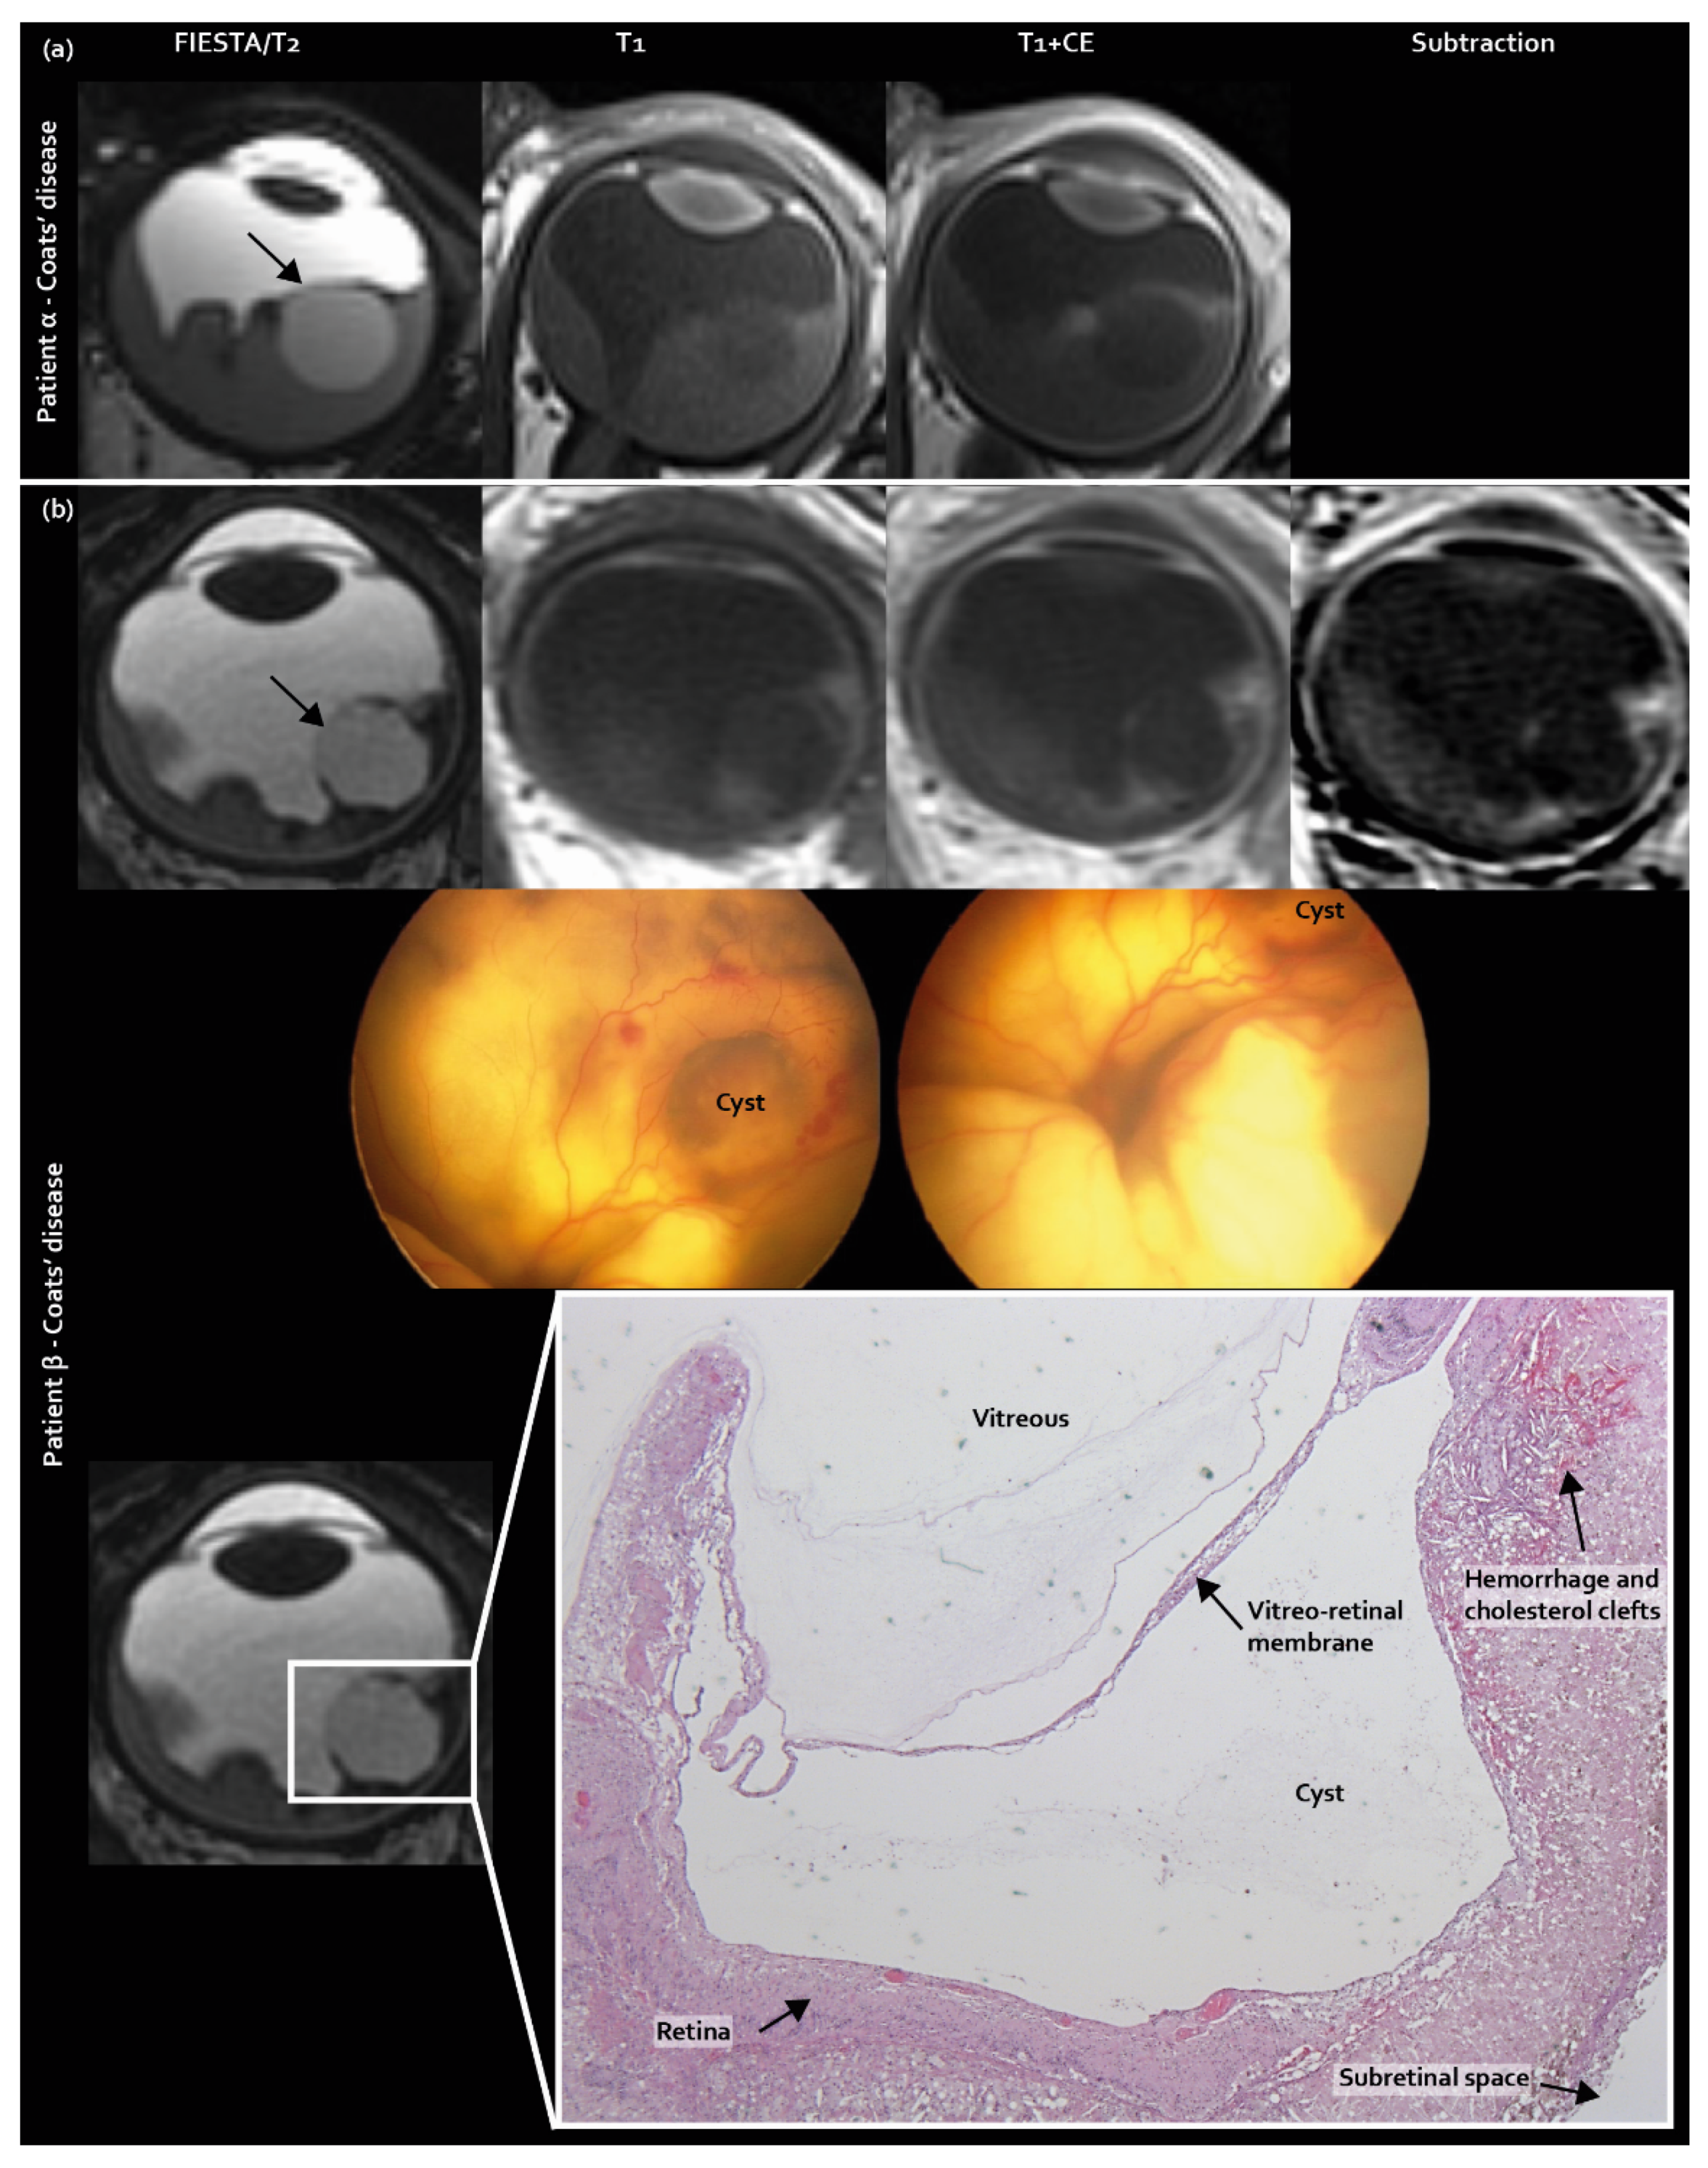

Three new features were identified as guiding towards pseudoretinoblastoma diagnosis: intraretinal macrocysts, contrast enhancement outside the solid lesion, and subfoveal enhancing nodules. Intraretinal macrocysts, incorporated in the scoring list, were found in 38% (9/24) of Coats’ disease eyes, compared with 20% (2/10) of PFV/retinal dysplasia eyes and 0% (0/34) of retinoblastoma eyes (corrected p = 0.005, Figure 1).

Figure 1.

Intraretinal macrocysts as a newly identified MR imaging feature exclusively found in pseudoretinoblastoma (Coats’ disease and PFV/retinal dysplasia): (a) MR imaging of an intraretinal macrocyst in Coats’s disease patient α; (b) MR imaging of an intraretinal macrocyst with corresponding Retcam fundus camera images and histopathology of Coats’ disease patient β.

Three new differentiating features were identified in this study. Firstly, intraretinal macrocysts were frequently found in pseudoretinoblastoma, predominantly in Coats’ disease. In Coats’ disease, cysts are caused by the exudation of lipids from abnormal vessels and have been reported in 11% of Coats’ disease cases in ophthalmological and pathology reports [28]. Cysts are related to prolonged retinal detachment and probably progress from more subtle intraretinal exudation (they have a prevalence of 35% in stage 2B Coats disease), towards intraretinal macrocysts that can be depicted by MR imaging. Cysts that are located intralesionally can be encountered in other retinal masses, including medulloepithelioma and cavitary retinoblastoma. The latter is an uncommon presentation of a well-differentiated retinoblastoma characterized by an endophytic growth pattern and cysts located intralesionally [29].